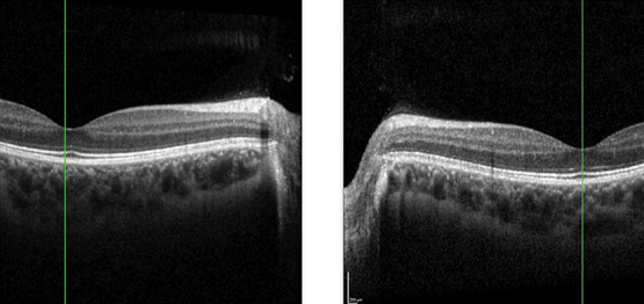

Is this a retinal detachment?

Rathin Pujari

,

Mohammed Haque

·

1st April 2021

Education

Case Reports